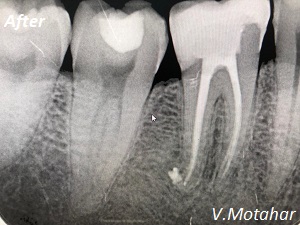

Root Canal Treatment on a molar tooth!

before

after

Root Canal treatment on Lower molar tooth immediate after the Root Filling!